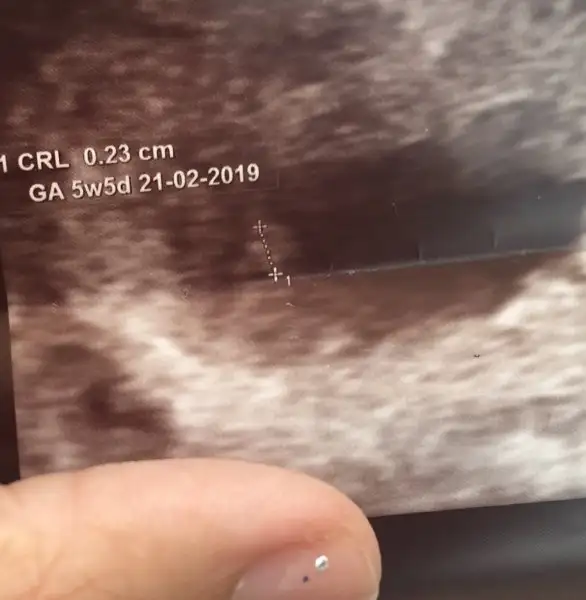

Dun gittim tatlim bi hafta once cocuk 6 7 haftaydi AMA dun 5 haftalik dedi kalp icin goruntusunu gorduk yanip sonen ama atisini duymadik canim kucuk diye acmadi..sende 3temmuzda haber et beniTeşekkür ederim tatlım, neden durduğunu bilemiyoruz, dr yediğin bir şeyden bile olabilir demişti, bir gün önce gece hissetmiştim ama, uykumdan sıçramıştımgenetik test yaptırmadım, şimdi önlem olsun diye coraspin içiyorum, dr vermedi ama genellikle kayıbı olanlara öneriyor doktorlar, bende de hafif pko var, geç döllenme olabiliyor pkolularda, sen ne zaman kontrole gideceksin.